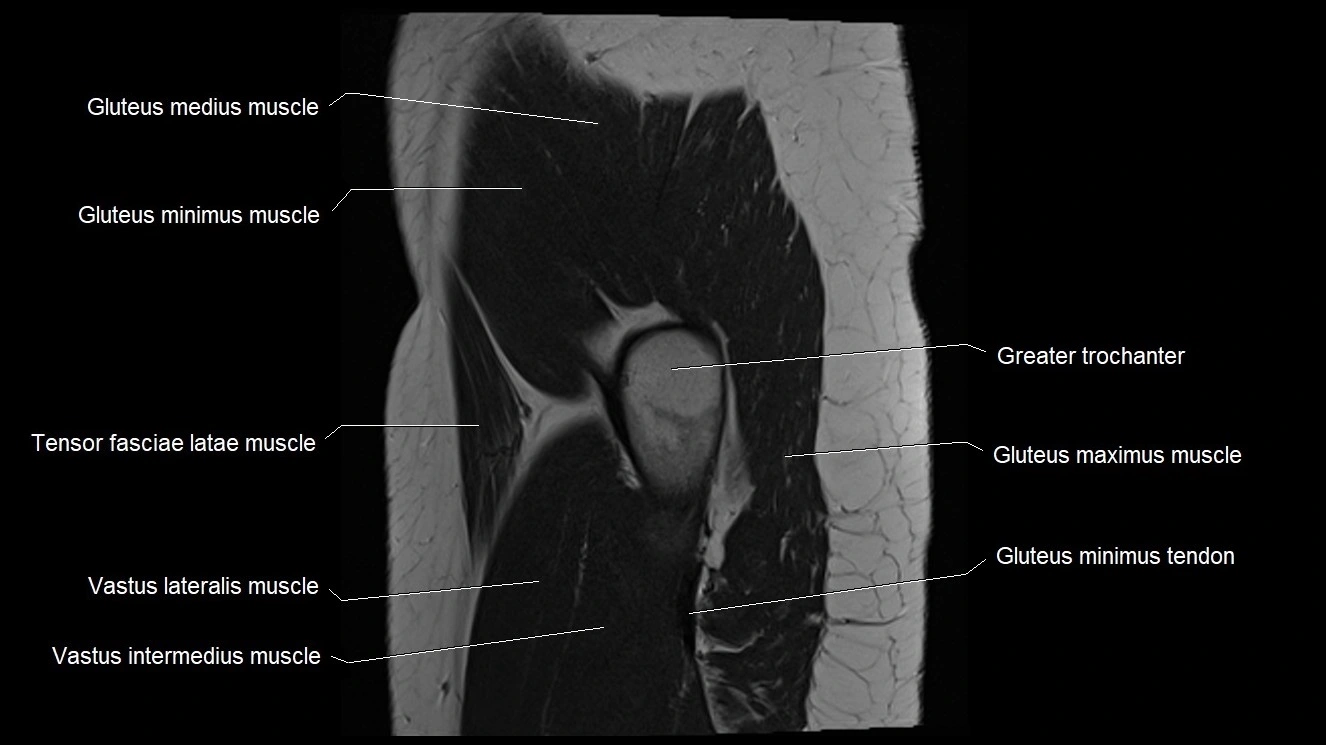

- Gluteus maximus muscle

- Gluteus medius muscle

- Gluteus minimus muscle

- Gluteus minimus tendon

- Greater trochanter

- Iliotibial tract

- Tensor fasciae latae muscle

- Vastus intermedius muscle

- Vastus lateralis muscle